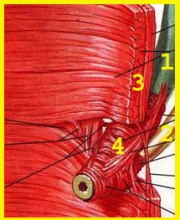

| 11:17, 27 במאי 2013 | Gallbladder14.jpg (קובץ) |  |

36 קילו־בייטים | Zvi kaufman | 2 | |

| 11:15, 27 במאי 2013 | Gallbladder6.jpg (קובץ) |  |

56 קילו־בייטים | Zvi kaufman | 2 | |

| 11:10, 27 במאי 2013 | Gallbladder5.jpg (קובץ) |  |

61 קילו־בייטים | Zvi kaufman | 4 | |

| 11:02, 27 במאי 2013 | Gallbladder4.jpg (קובץ) |  |

33 קילו־בייטים | Zvi kaufman | 2 | |

| 11:00, 27 במאי 2013 | Gallbladder3.jpg (קובץ) |  |

62 קילו־בייטים | Zvi kaufman | 2 | |

| 10:59, 27 במאי 2013 | Gallbladder2.jpg (קובץ) |  |

176 קילו־בייטים | Zvi kaufman | 2 | |

| 10:57, 27 במאי 2013 | Gallbladder1.jpg (קובץ) |  |

43 קילו־בייטים | Zvi kaufman | 2 | |

| 04:13, 23 במאי 2013 | Gallbladder13.jpg (קובץ) |  |

29 קילו־בייטים | Zvi kaufman | שוחזר לגרסה מ־04:11, 23 במאי 2013 | 5 |